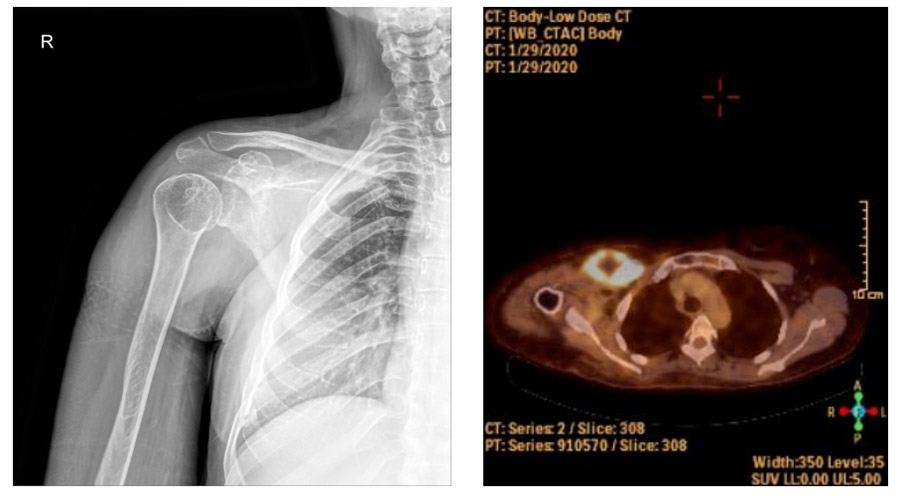

Ameliyat Öncesi: Röntgende özellik yok iken PET-CT’de artmış yoğun aktivite görülmekte